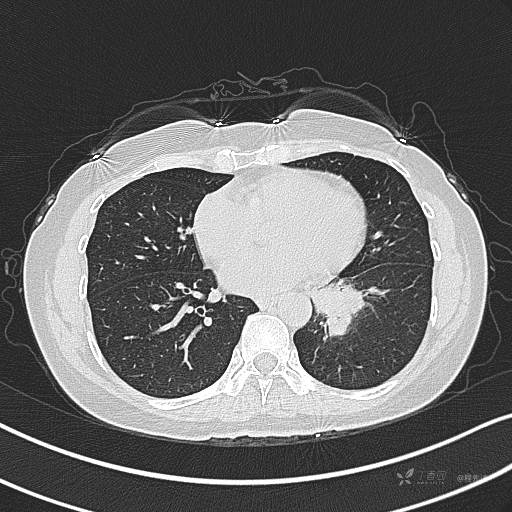

增强动脉期

动脉期CT值约74HU